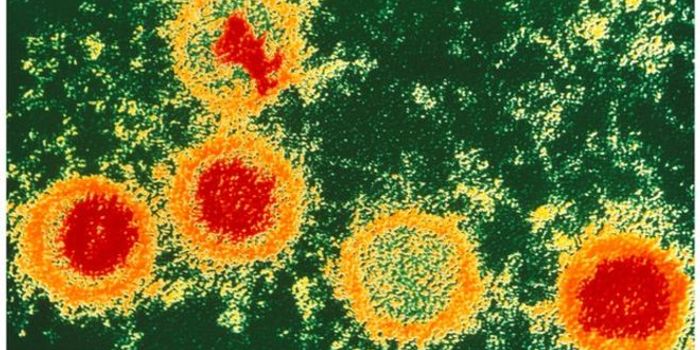

FEB 16, 2017MicrobiologySpoiler alert, you’re infected with Epstein-Barr virus. Well, you’re probably infected - nearly 98% of peopl ...

SEP 30, 2015ImmunologyCurrently in the United States, 13 percent of the 1.2 million people infected with HIV are unaware of their condition (A ...

NOV 06, 2020Drug Discovery & DevelopmentThe World Health Organization estimates that over 500 million people have Herpes Simplex Virus Type 2 (HSV-2), a sexuall ...